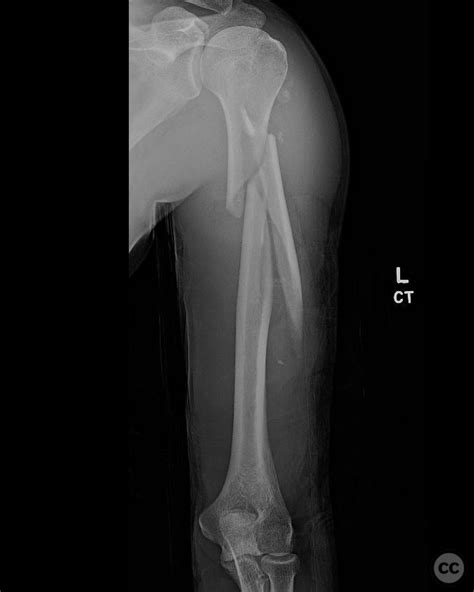

Types of Humerus Bone Breaks

Humerus bone breaks can be classified based on their location and pattern. Common types include:

Proximal Humerus Fracture Occurs near the shoulder joint, often involving the head or neck of the humerus.

Humeral Shaft Fracture Affects the middle section of the humerus, often due to direct trauma.

Distal Humerus Fracture Occurs near the elbow joint, often involving the condyles or epicondyles.

📝 Note: The type of fracture can influence the treatment approach and recovery time.